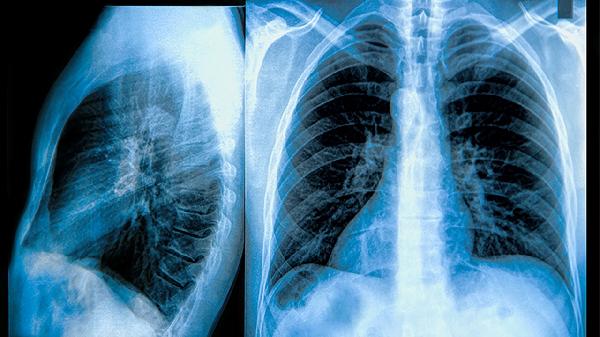

慢性阻塞性肺疾病的核心病理改变是气道壁增厚、黏液分泌增多以及肺泡结构破坏,导致呼气时气道塌陷。患者常出现活动后气短,随着病情进展,静息状态下也会感到呼吸困难。典型肺功能检查显示第一秒用力呼气容积与用力肺活量比值降低,这种气流受限呈不完全可逆性。